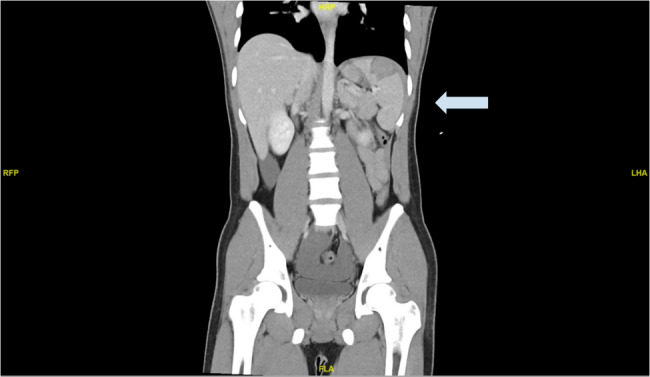

Case presentation: The patient is a 21-year-old male, with no known chronic disease. He is a smoker and complained of a persistent cough for the past three months. He presented the day after a gym session, with sudden left hypochondrium tenderness with no history of trauma, vomiting or diarrhoea. Physical exam revealed normal vital signs and generalized involuntary guarding over the entire abdomen. Initial point-of-care ultrasound was negative for free fluid in the abdomen, but a repeat ultrasound three hours later turned positive. Computed tomography scans of the abdomen, pelvis and mesenteric angiogram were then performed. They revealed intraperitoneal blood, a Grade III splenic haematoma involving the superior pole of the spleen towards the inferior pole, but no active bleeding. The patient was admitted for close monitoring. Initial laboratory evaluation did not show any coagulopathy or infection. The patient remained hemodynamically stable throughout his inpatient stay, and was managed conservatively with rest, analgesia, and empirical antibiotics. Serial haemoglobin levels remained stable, and his symptoms resolved with analgesia. As he remained hemodynamically stable, no repeat imaging was performed inpatient. He was subsequently discharged with instructions to avoid strenuous activities for 4 to 6 weeks. An outpatient follow-up was arranged for him, to review symptoms and monitor haemoglobin level.